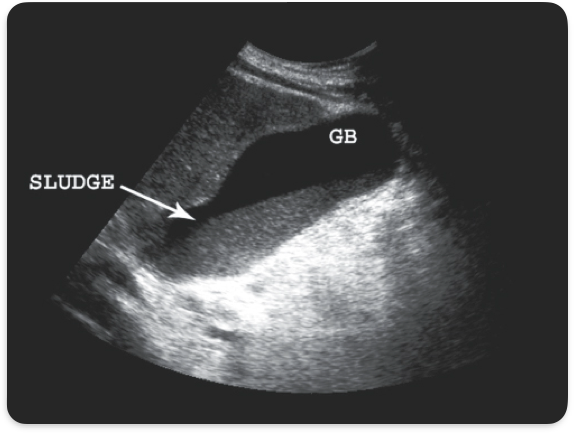

Sludge

Viscid bile, due to biliary stasis

Gallbladder sludge

Sludge with stones